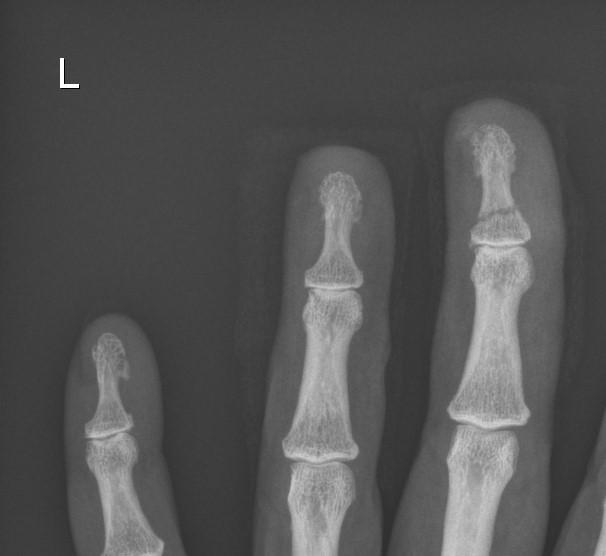

Case Study - Distal Phalanx Fracture

This 53 year old woman accidentally caught her fingers in a moving stick blender - she lacerated two fingertips, and sustained a neat transverse fracture of the distal phalanx in her middle finger. She counts herself lucky to still have all her fingers more-or-less intact! We fitted her with a neat protective thermoplastic splint for the fractured digit, and look forward to working with her in the coming weeks to ensure her scars are well healed and desensitised, her fingers are moving freely, and the full functional capacity of her hand is restored.